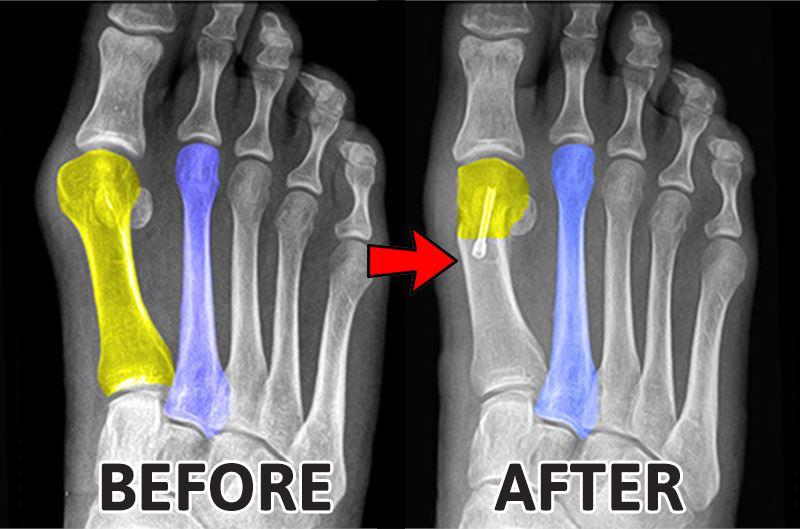

👉Are You Experiencing Heel Pain? Are The Toes Of Your Feet Not Straight?

Spreading your five toes is one of the best ways to help your feet align correctly and reduce foot pain.

- SPEARD YOUR TOES

It help with post-surgical and post-sclerotherapy treatment, they are great for correcting the deformations of the feet and the tailor’s bunions.